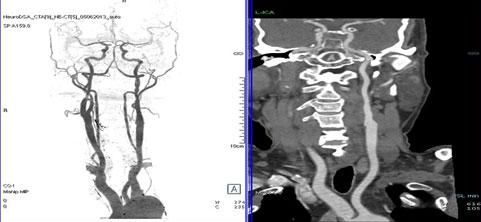

二、多層螺旋CT頭頸部及體部血管成像技術:

該機掃描覆蓋範圍廣、時間短,多種後處理分析軟件能顯示各血管細小分支,可以清晰顯示動脈瘤、動脈夾層、血管畸形、血管狹窄及動脈粥樣硬化斑塊等,适用于頭頸部血管成像、肺動脈成像、胸腹部血管成像及四肢血管成像。

1.顱腦血管成像:

動脈瘤

2、頸部血管成像

3、肺動脈血管成像:

4、腎動脈血管成像(腎動脈狹窄):

5、下肢動脈血管成像: